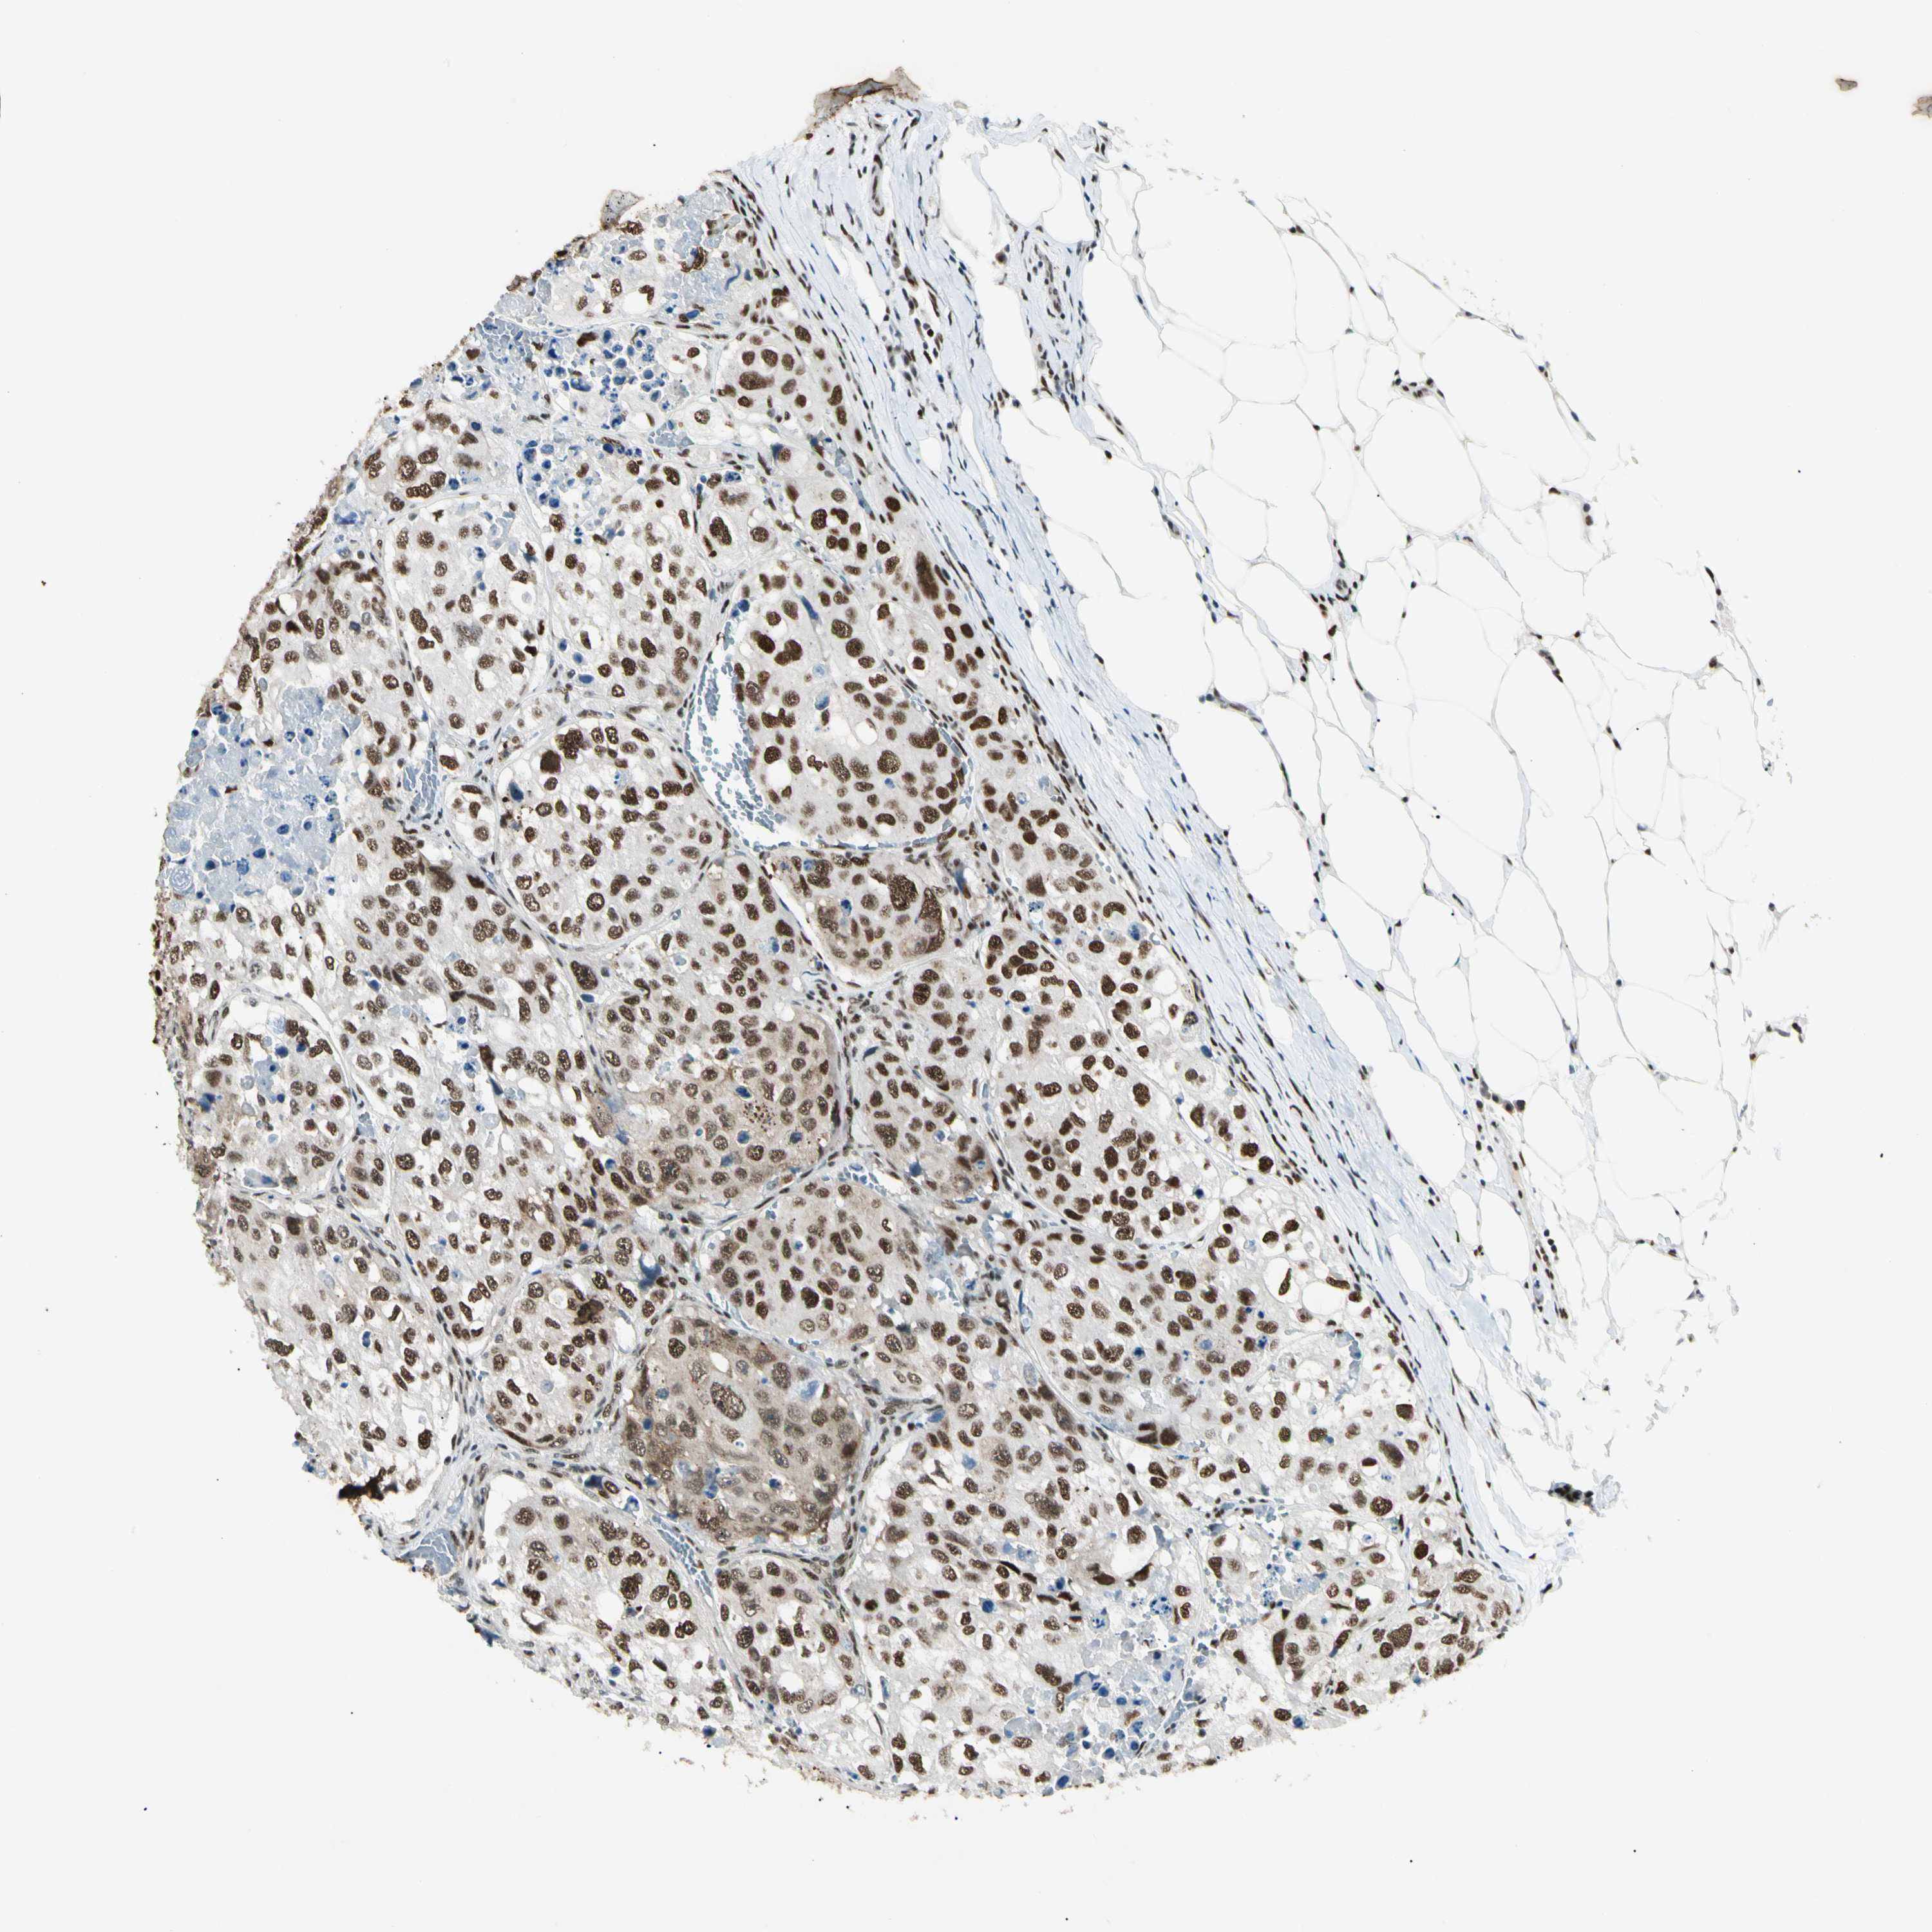

UROTHELIAL CANCER - Protein expressioni

A mouse-over function shows sample information and annotation data. Click on an image to view it in a full screen mode. Samples can be filtered based on level of antibody staining by selecting one or several of the following categories: high, medium, low and not detected. The assay and annotation is described here.

Note that samples used for immunohistochemistry by the Human Protein Atlas do not correspond to samples in the TCGA dataset.

Antibody stainingi

Antibody staining in the annotated cell types in the current human tissue is reported as not detected, low, medium, or high, based on conventional immunohistochemistry profiling in selected tissues. This score is based on the combination of the staining intensity and fraction of stained cells.

Each image is clickable and will lead to virtual microscopy that enables deeper exploration of all samples and also displays staining intensity scores, fraction scores and subcellular localization as well as patient and tissue information for each sample.

Antibody HPA008784

Antibody CAB033036

Antibody CAB058691

Staining

High

Medium

Low

Not detected

Intensity

Strong

Moderate

Weak

Negative

Quantity

>75%

75%-25%

<25%

None

Location

Nuclear

Cytoplasmic/membranous

Cytoplasmic/membranous,nuclear

Urothelial carcinoma, Low grade

Urothelial carcinoma, High grade

Urothelial carcinoma, NOS